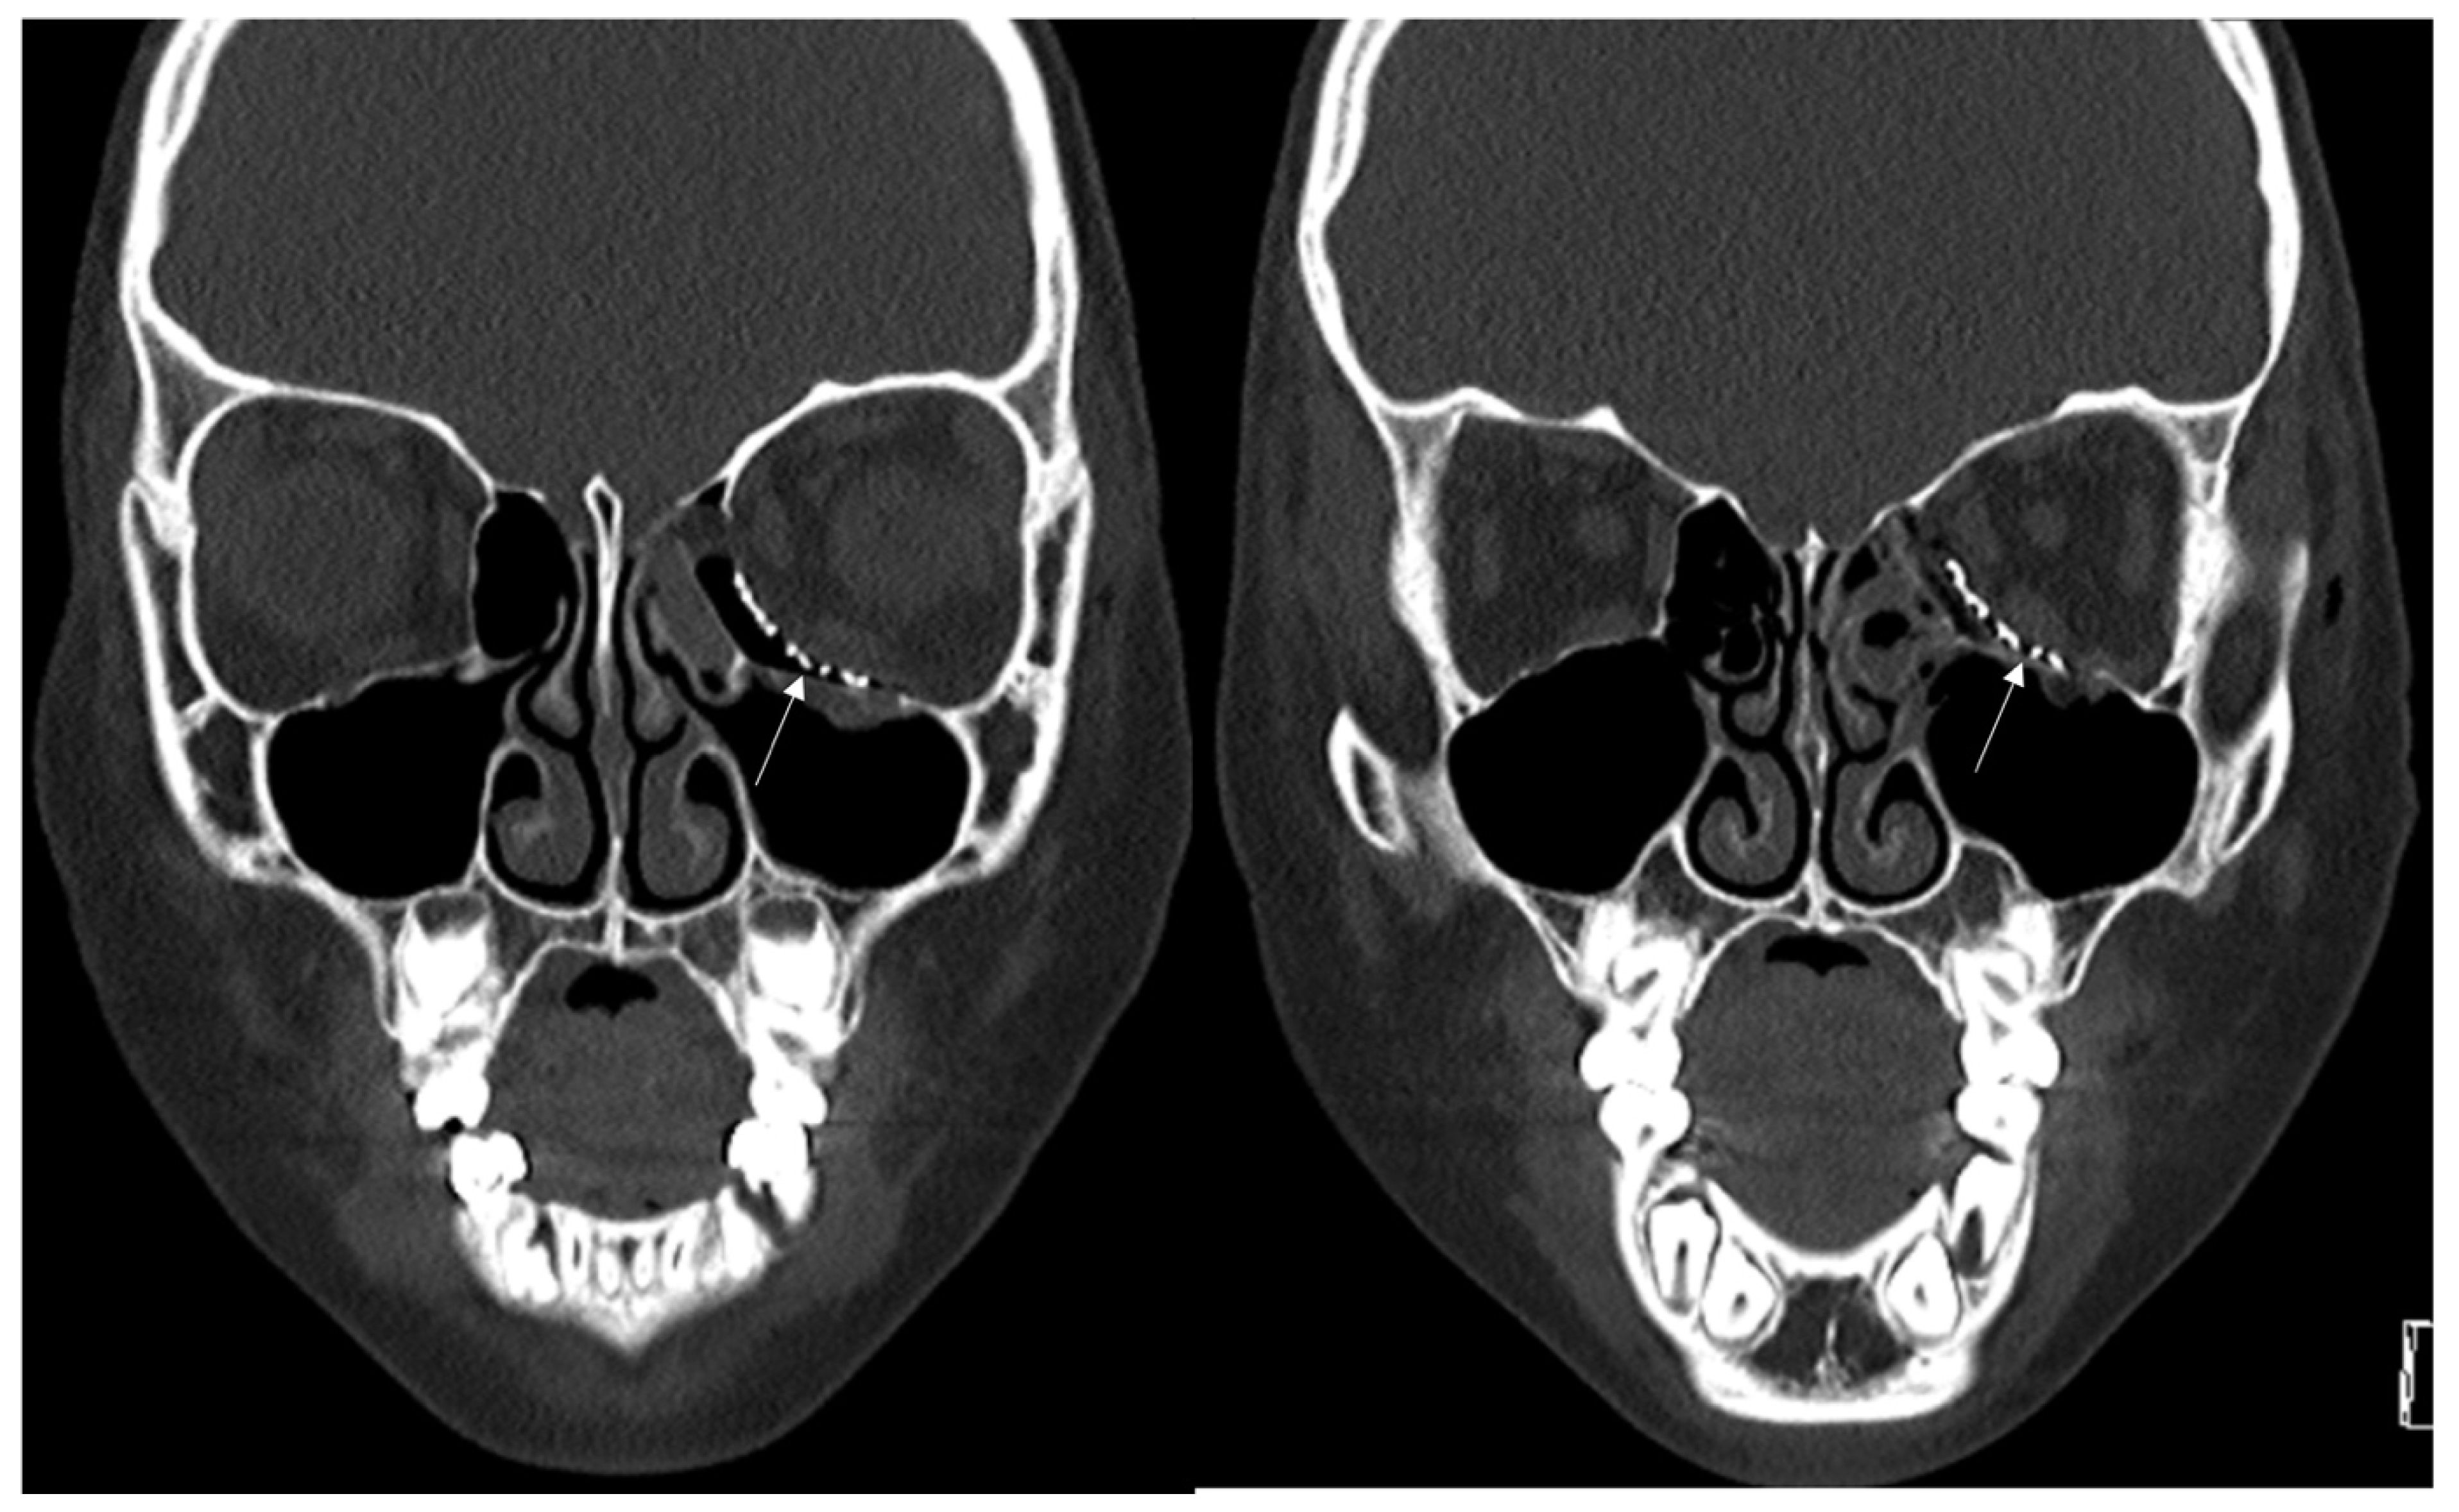

The preoperative (a) and postoperative (b) CT of the left orbital floor Titanium Plate Orbital Fracture — 3d preformed titanium meshes can reconstruct inferomedial fractures with the same accuracy as customized. — orbital trauma is a frequent cause of damage to both bony, soft tissue and neurovascular structures in the. — we use titanium mesh to repair orbital wall defects and titanium plate to repair fractures of orbital margin and. — orbital. Titanium Plate Orbital Fracture.